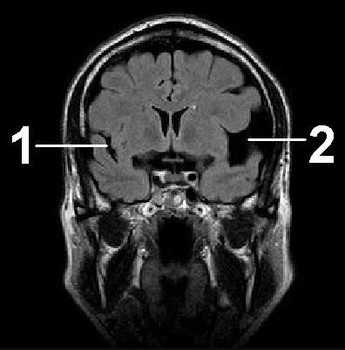

ΠΡΠ΅Π΄ΡΡΠ°Π²Π»Π΅Π½Π½Π°Ρ ΠΏΠ°ΡΠΎΠ»ΠΎΠ³ΠΈΡ Ρ Π²Π·ΡΠΎΡΠ»ΡΡ Π΄ΠΈΠ°Π³Π½ΠΎΡΡΠΈΡΡΠ΅ΡΡΡ ΡΠ΅Π΄ΠΊΠΎ. ΠΠ½Π° ΠΌΠΎΠΆΠ΅Ρ Π±ΡΡΡ Π²ΡΠΎΠΆΠ΄Π΅Π½Π½ΠΎΠΉ ΠΈΠ»ΠΈ ΠΏΡΠΈΠΎΠ±ΡΠ΅ΡΡΠ½Π½ΠΎΠΉ Π² ΡΠ΅Π·ΡΠ»ΡΡΠ°ΡΠ΅ ΠΌΠΈΠΊΡΠΎΠΈΠ½ΡΡΠ»ΡΡΠ°. ΠΠ»Ρ ΠΏΠΎΡΡΠ°Π½ΠΎΠ²ΠΊΠΈ Π΄ΠΈΠ°Π³Π½ΠΎΠ·Π° ΠΏΠ°ΡΠΈΠ΅Π½ΡΠ° ΠΎΡΠΏΡΠ°Π²Π»ΡΡΡ Π½Π° ΠΠ’ ΠΈ ΠΠ Π’ Π΄Π²ΡΡ ΠΏΠΎΠ»ΡΡΠ°ΡΠΈΠΉ. Π’Π΅ΡΠ°ΠΏΠΈΡ Π½ΠΎΡΠΈΡ Π²ΠΎΡΡΡΠ°Π½ΠΎΠ²ΠΈΡΠ΅Π»ΡΠ½ΡΠΉ Ρ Π°ΡΠ°ΠΊΡΠ΅Ρ. ΠΠ»Ρ ΡΡΠΎΠ³ΠΎ ΠΈΡΠΏΠΎΠ»ΡΠ·ΡΡΡ ΠΌΠ΅Π΄ΠΈΠΊΠ°ΠΌΠ΅Π½ΡΡ, ΠΊΠΎΡΠΎΡΡΠ΅ ΠΏΡΠΈΠ²ΠΎΠ΄ΡΡ Π² Π½ΠΎΡΠΌΡ ΠΊΡΠΎΠ²ΠΎΡΠΎΠΊ ΠΈ ΠΎΠ±ΠΌΠ΅Π½Π½ΡΠ΅ ΠΏΡΠΎΡΠ΅ΡΡΡ.